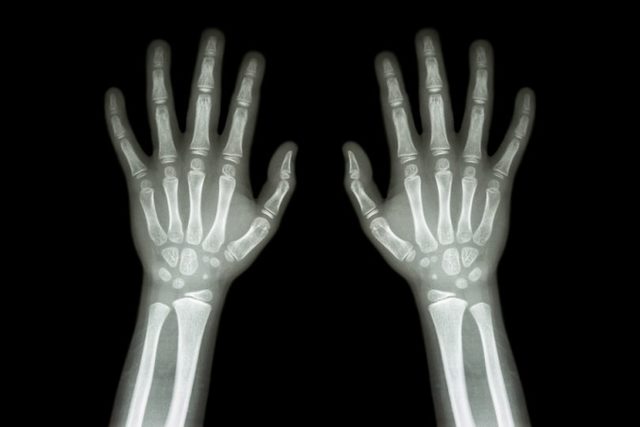

Los primeros equipos de mamografía fueron adaptaciones realizadas a los equipos de radiología. En 1980 llega al país la xeroradiografía que se aplicó fundamentalmente en los estudios de los problemas de seno así como en la localización de cuerpos extraños de partes blandas.